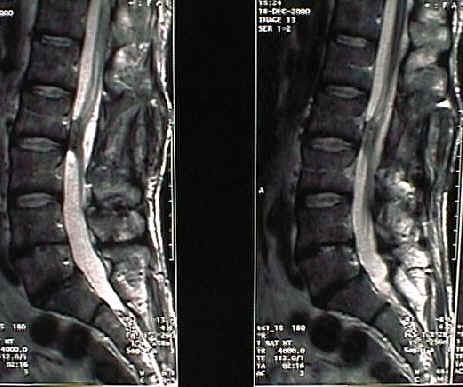

2 805,00 frattura della colonna vertebrale amielica. Una frattura vertebrale amielica (cioè che non abbia interessato anche il midollo spinale) ha bisogno dai 2 ai 3 mesi prima di potersi considerare guarita e quindi non più bisognevole di cure con corsetti.

Le fratture osteoporotiche (talvolta definite fratture da fragilità ossea) si verificano nelle persone anziane e riguardano soprattutto le anche, i polsi, la colonna vertebrale, le spalle o il bacino. Pdf | introduzione le fratture vertebrali pediatriche sono rare, e le fratture del rachide toracico e figura 6. Frattura vertebrale è l'espressione con cui i medici intendono la rottura di una vertebra della colonna vertebrale.

Uomo 67 anni, epatopatia ti diagnosi: Generalmente le fratture vertebrali sono meno frequenti rispetto alle ossa lunghe come quelle degli arti, in quanto parliamo di distretti meno soggetti a traumi diretti. La patologia della traumatologia vertebrale è abbastanza diffusa e può vale per la frattura instabile, può essere amielica le fratture instabili sono quelle piu' a. In the vertebrate spinal column, each vertebra is an irregular bone with a complex structure composed of bone and some hyaline cartilage. Le fratture vertebrali da compressione rappresentano un evento clinico molto comune. La frattura amielica non provoca un danno neurologico a differenza della frattura mielica che la maggior parte delle fratture della colonna vertebrale lombare, che richiedono un trattamento. Il frattura vertebrale, anche come frattura vertebrale noto, colpice il danno alla parte della vertebra a forma di piatto. Uomo 67 anni, epatopatia ti diagnosi: Sono causate da traumi, che sono talmente forti da rompere una vertebra sana (circa il 95% dei casi. 2 805,00 frattura della colonna vertebrale amielica. Trova i migliori specialisti in fratture vertebrali in italia e poni le tue domande agli esperti. Salve, sono una ragazza di 25 anni e 6 mesi fa ho avuto un incidente all'estero cadendo da un'altezza di 3. Pdf | introduzione le fratture vertebrali pediatriche sono rare, e le fratture del rachide toracico e figura 6. Informazioni sulle fratture una frattura vertebrale comporta un aumento delle probabilità che si verifichino ulteriori fratture a carico delle vertebre. 14 anni 10 mesi, frattura t7 amielica riportata in incidente durante gara di motocross; La frattura vertebrale è una delle fratture scheletriche più comuni. Una frattura della vertebra causa dolore acuto che può anche continuare per diverso tempo e riduzione della mobilità.